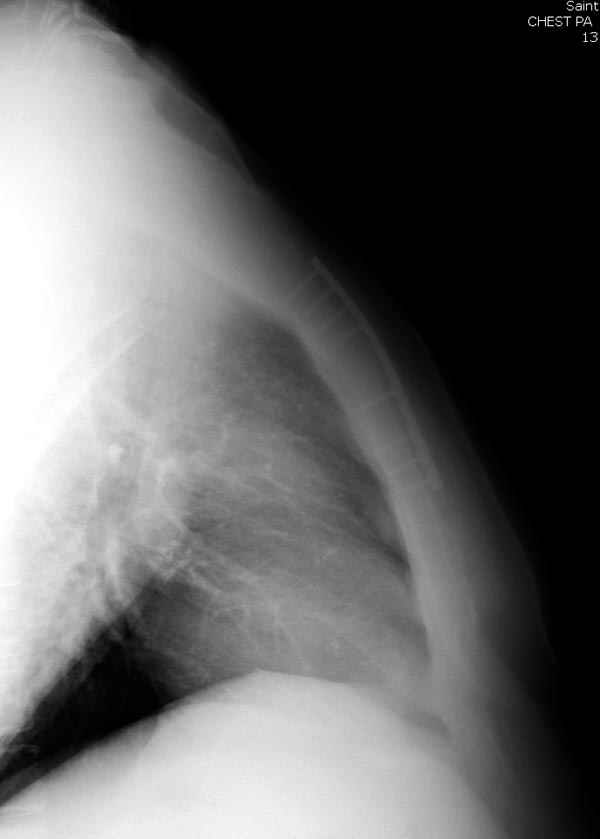

Оперировали вместе с грудным хирургом и в нашем случае главной причиной была болезненность. Во время операции приняли все меры предосторожности недопущения прокола средостения (см. на 4 снимке близкий контур сердца!!)

Ложный сустав зафиксирован двумя пластинами 2.4 мм (locking plate) позаимствованными из челюстно-лицевой хирургии, с костной пластикой, все остальные пластины мне показались слишком толстыми, грубые для грудины или отсутсвовали возможности создания угловой стабильности.

Рентген снимки во время операции и последние сделаны на днях.